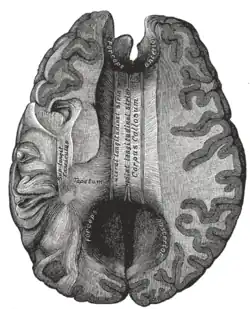

Corpus callosum from above, front part at the top of the image

The corpus callosum forms the floor of the longitudinal fissure that separates the two cerebral hemispheres. Part of the corpus callosum forms the roof of the lateral ventricles.[5]

The corpus callosum has four main parts – individual nerve tracts that connect different parts of the hemispheres. These are the rostrum, the genu, the trunk or body, and the splenium.[4] Fibres from the trunk and the splenium, known together as the tapetum ("carpet"), form the roof of each lateral ventricle.[6]